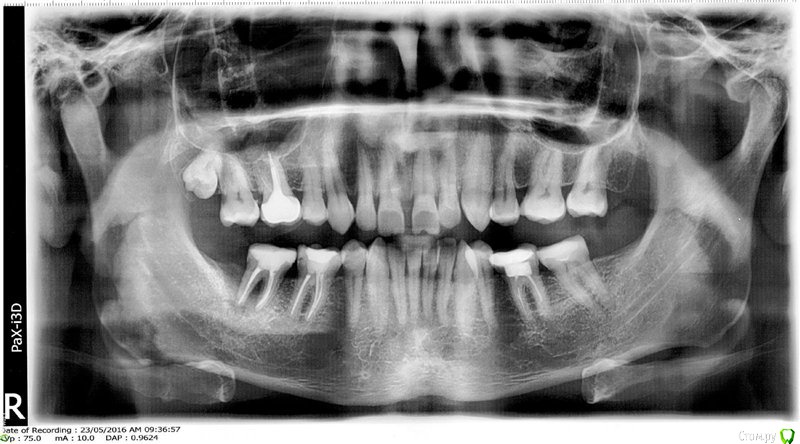

Slava76 Опубликовано 26 сентября, 2016 Поделиться Опубликовано 26 сентября, 2016 Всем доброго дня! Удалили мне еще в мае коренной зуб. Сейчас хочу ставить имплант. Сходил на консультацию к врачу. Мне сказали, что нужно ставить два импланта. Аргументация следующая. Удаленный зуб достаточно большой (хотя на мой взгляд обычный коренной зуб), и что такого размера имплантов не бывает. Перерыл весь интернет, нечего похожего не встретил. Подскажите, действительно такое может быть?На снимке, это нижний левый зуб.P.s. накладно вместо одного зуба, сразу два импланта делать... ¶ Ссылка на комментарий

dok1 Опубликовано 26 сентября, 2016 Поделиться Опубликовано 26 сентября, 2016 47 зуб обычный по размеру. Но для адекватного восстанавления ф-ии нужно ставить два импланта и две коронки. Уто особенность топографии зубов верхней и нижней челюсти с этой стороны. А вы можете выбрать любой вариант. Второй имплант через силу ставить вам никто не будет. Ссылка на комментарий

колесников Опубликовано 26 сентября, 2016 Поделиться Опубликовано 26 сентября, 2016 Есть патология прикуса. Когда то была 8ка и она "сместила" соседние зубы. Если вы поставите 1 имплант,то нагружен будет только 1 верхний антагонист,а второй(крайний) будет "висеть"без дела. Чтобы разрешить этот вопрос,необходимо провести диагностику прикуса. Доктор ортопед снимет слепки,изготовит гипсовые модели челюстей и объяснит вам не на пальцах как будут работать "новые" зубы с уже имеющимися. Возможно понадобится консультация ортодонта. Ссылка на комментарий

Slava76 Опубликовано 26 сентября, 2016 Автор Поделиться Опубликовано 26 сентября, 2016 Помню в универе нам так говорили))) Врач, которая меня смотрела, к.м.н. и в мед. академии еще преподает, если верить ее резюме. Второй имплант через силу ставить вам никто не будет. Я на консультацию приходил со снимком и КТ. Врач, показывая мне на снимок и КТ, довольно логично показала, что от одного импланта, толку не будет никакого. Если ставить один имплант, то при замыкании челюсти, крайний верхний зуб будет висеть в воздухе. Но все это будет справедливо только в том случае, если имплант маленького размера. Вот я и пытаюсь понять, действительно ли не бывает имплантов размером с мой удаленный зуб? Есть патология прикуса. Когда то была 8ка и она "сместила" соседние зубы. Да. Проблема с прикусом у меня действительно есть. Но 8-ки у меня некогда не было. На снимке все зубы, которые у меня выросли. Из-за неправильного прикуса у меня стираются передние зубы, особенно верхние изнутри (на снимке это видно). Чтобы "приподнять" мой прикус, врач предложила мне поставить коронки на все нижние коренные зубы (эти зубы сейчас запломбированы, пломбам около 10 лет. Но два из трех пока нормальные, а на одном появилась трещинка). Коронки она сделает повыше, тем самым прикус станет не таким низким и передние зубы будут меньше стачиваться. Это действительно так? Ссылка на комментарий

dok1 Опубликовано 26 сентября, 2016 Поделиться Опубликовано 26 сентября, 2016 Импланта на два зуба в вашем случае нет. Поднимать прикус нужно одновременно на всех зубах. Нельзя приподнять прикус в одном участке, а остальные оставить без смыкания висящими в воздухе. Будут проблемы. Ссылка на комментарий